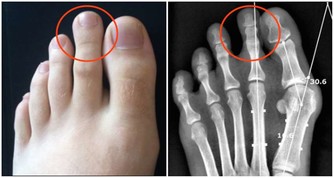

*****手腳症狀*****

腳上有開放性潰瘍腳上的開放性潰瘍會令人感到難以置信的疼痛,需要讓醫生盡快檢查,因為它們可能是一種名為主髂動脈閉塞性疾病的心髒病的跡象,即主動脈被堵塞了。這種病會導致缺血,使流向組織的血液和氧氣供應減少。缺血可能導致足部組織破裂,形成開放性潰瘍。

腳趾疼痛如果你經常在沒有明顯原因的情況下腳趾疼痛,並且在休息時注意到腿部寒冷或麻木,這也是主髂動脈閉塞性疾病的一個跡象。

腳、腳踝或腿腫脹腫脹通常是身體某一部位受傷所發出的信號,但組織中多餘體液的積累也可能是心力衰竭的跡象。當血液返回心臟被堵塞時,就會發生這種情況,它會導致組織腫脹。